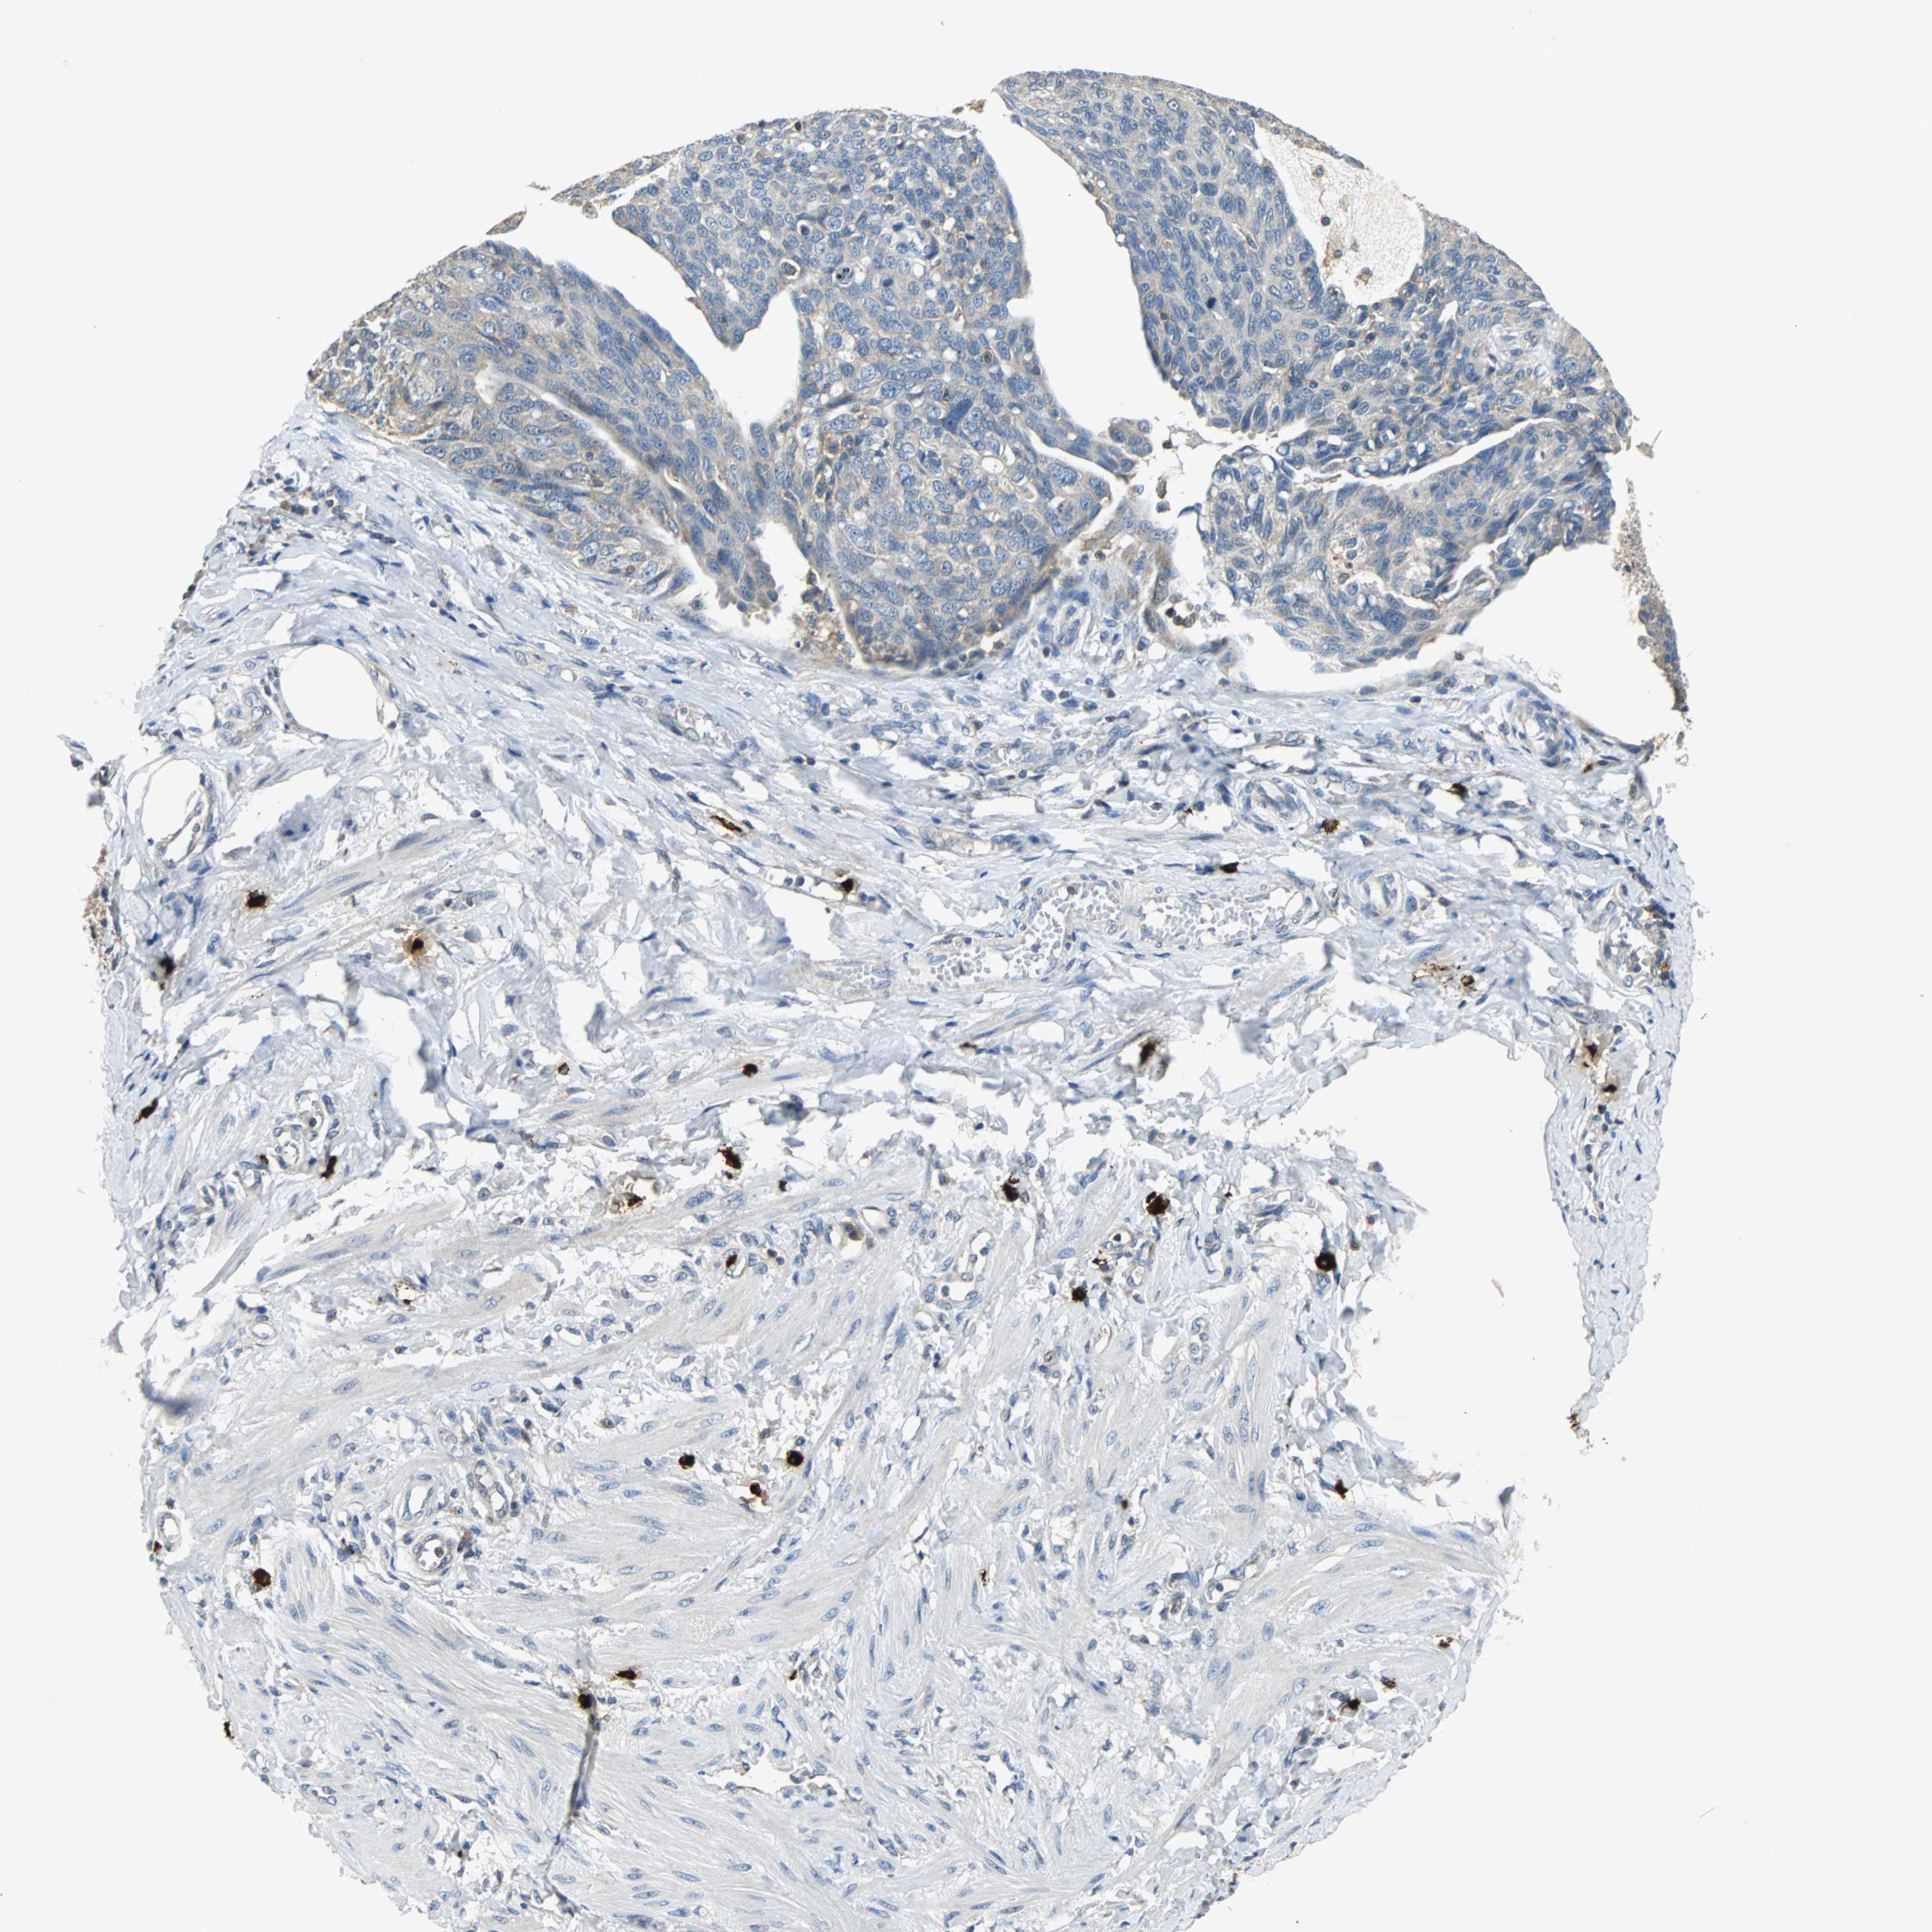

OVARIAN CANCER - Protein expressioni

A mouse-over function shows sample information and annotation data. Click on an image to view it in a full screen mode. Samples can be filtered based on level of antibody staining by selecting one or several of the following categories: high, medium, low and not detected. The assay and annotation is described here.

Note that samples used for immunohistochemistry by the Human Protein Atlas do not correspond to samples in the TCGA dataset.

Antibody stainingi

Antibody staining in the annotated cell types in the current human tissue is reported as not detected, low, medium, or high, based on conventional immunohistochemistry profiling in selected tissues. This score is based on the combination of the staining intensity and fraction of stained cells.

Each image is clickable and will lead to virtual microscopy that enables deeper exploration of all samples and also displays staining intensity scores, fraction scores and subcellular localization as well as patient and tissue information for each sample.

Antibody HPA006479

Antibody HPA008689

Antibody CAB020712

Cystadenocarcinoma, serous, NOS

Carcinoma, endometroid

Carcinoma, NOS

Cystadenocarcinoma, mucinous, NOS